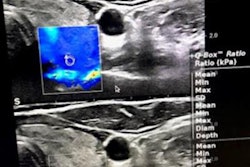

Hashimoto's thyroiditis and Graves' disease are autoimmune diseases that affect the thyroid gland. Ultrasound findings and autoantibody elevation are typically used to diagnose either disease. In rare cases, ultrasound findings may be normal in both diseases, but previous research has suggested that shear-wave velocity values from elastography are higher in autoimmune thyroiditis than in healthy thyroid glands.

Bitkin and Toprak explored the use of elastography in 88 pediatric patients with Hashimoto's thyroiditis and Graves' disease. Out of these, 28 had Hashimoto's thyroiditis, 20 had Graves' disease, and the remaining 40 were healthy controls. All patients underwent thyroid elastography and ultrasound.

The duo found that shear-wave velocity values of patients with either disease showed higher thyroid tissue stiffness than healthy controls, but when such values were compared between both diseases, the team found no significant difference (p = 0.73). As for conventional ultrasound, patients with Hashimoto's thyroiditis had a hypoechoic echo pattern similar to those with Graves' disease (p < 0.05).